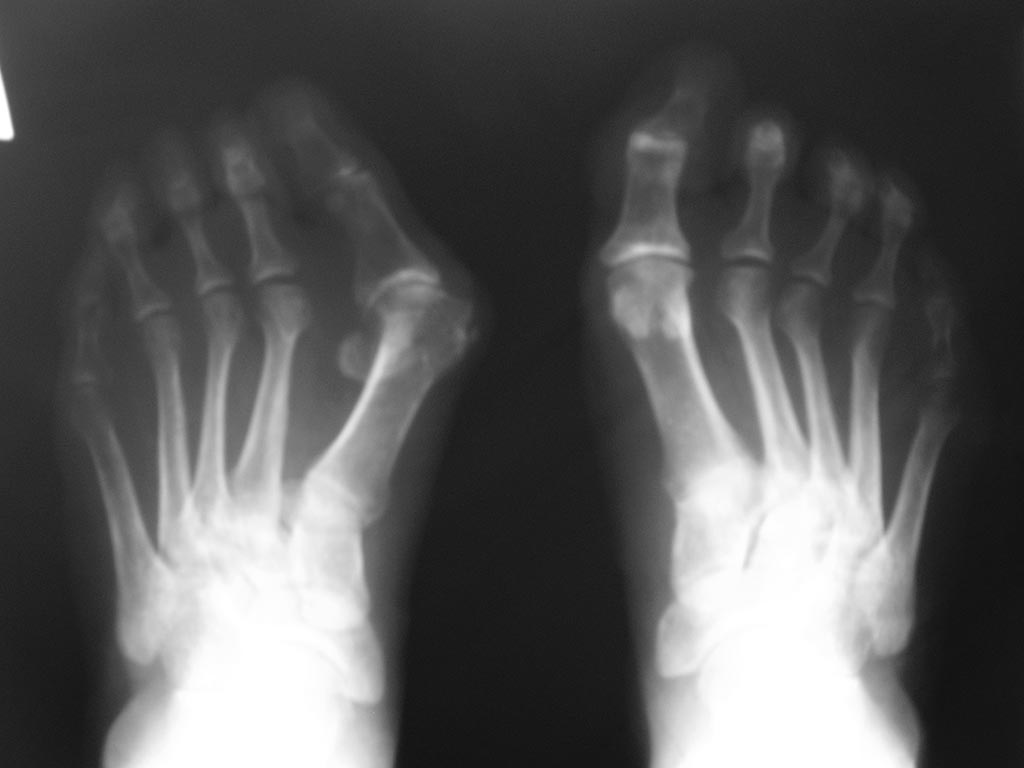

Здравствуйте,коллеги! Хотелось бы обсудить данный случай. Прошу помочь

определиться с объемом реконструкции переднего отдела левой стопы.

Женщина 50 лет, работа на ногах. Первый палец довольно ригиден в своей

установке. Плотные натоптыши на подошве.

Планируется остеотомия 1 плюсневой кости- Z-образная или поперечная,

резекция экзостоза, формирование поперечного свода при помощи

аллотрансплантата. Интересует- стоит ли делать резекцию основания

основной фаланги, если 1 палец не будет "выводиться" в правильное

положение, либо переместить сухожилие разгибателя кнаружи.